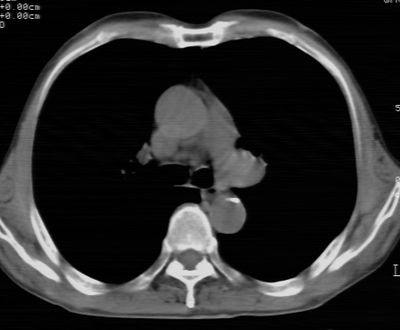

标题: CT24783:m71,既往肺心病史3年,现咳嗽,憋喘。 [打印本页]

标题: CT24783:m71,既往肺心病史3年,现咳嗽,憋喘。

1)左肺上叶周围型肺癌可能。2)两肺全小叶型肺气肿。

左上周围型肺癌,全小叶型肺气肿。